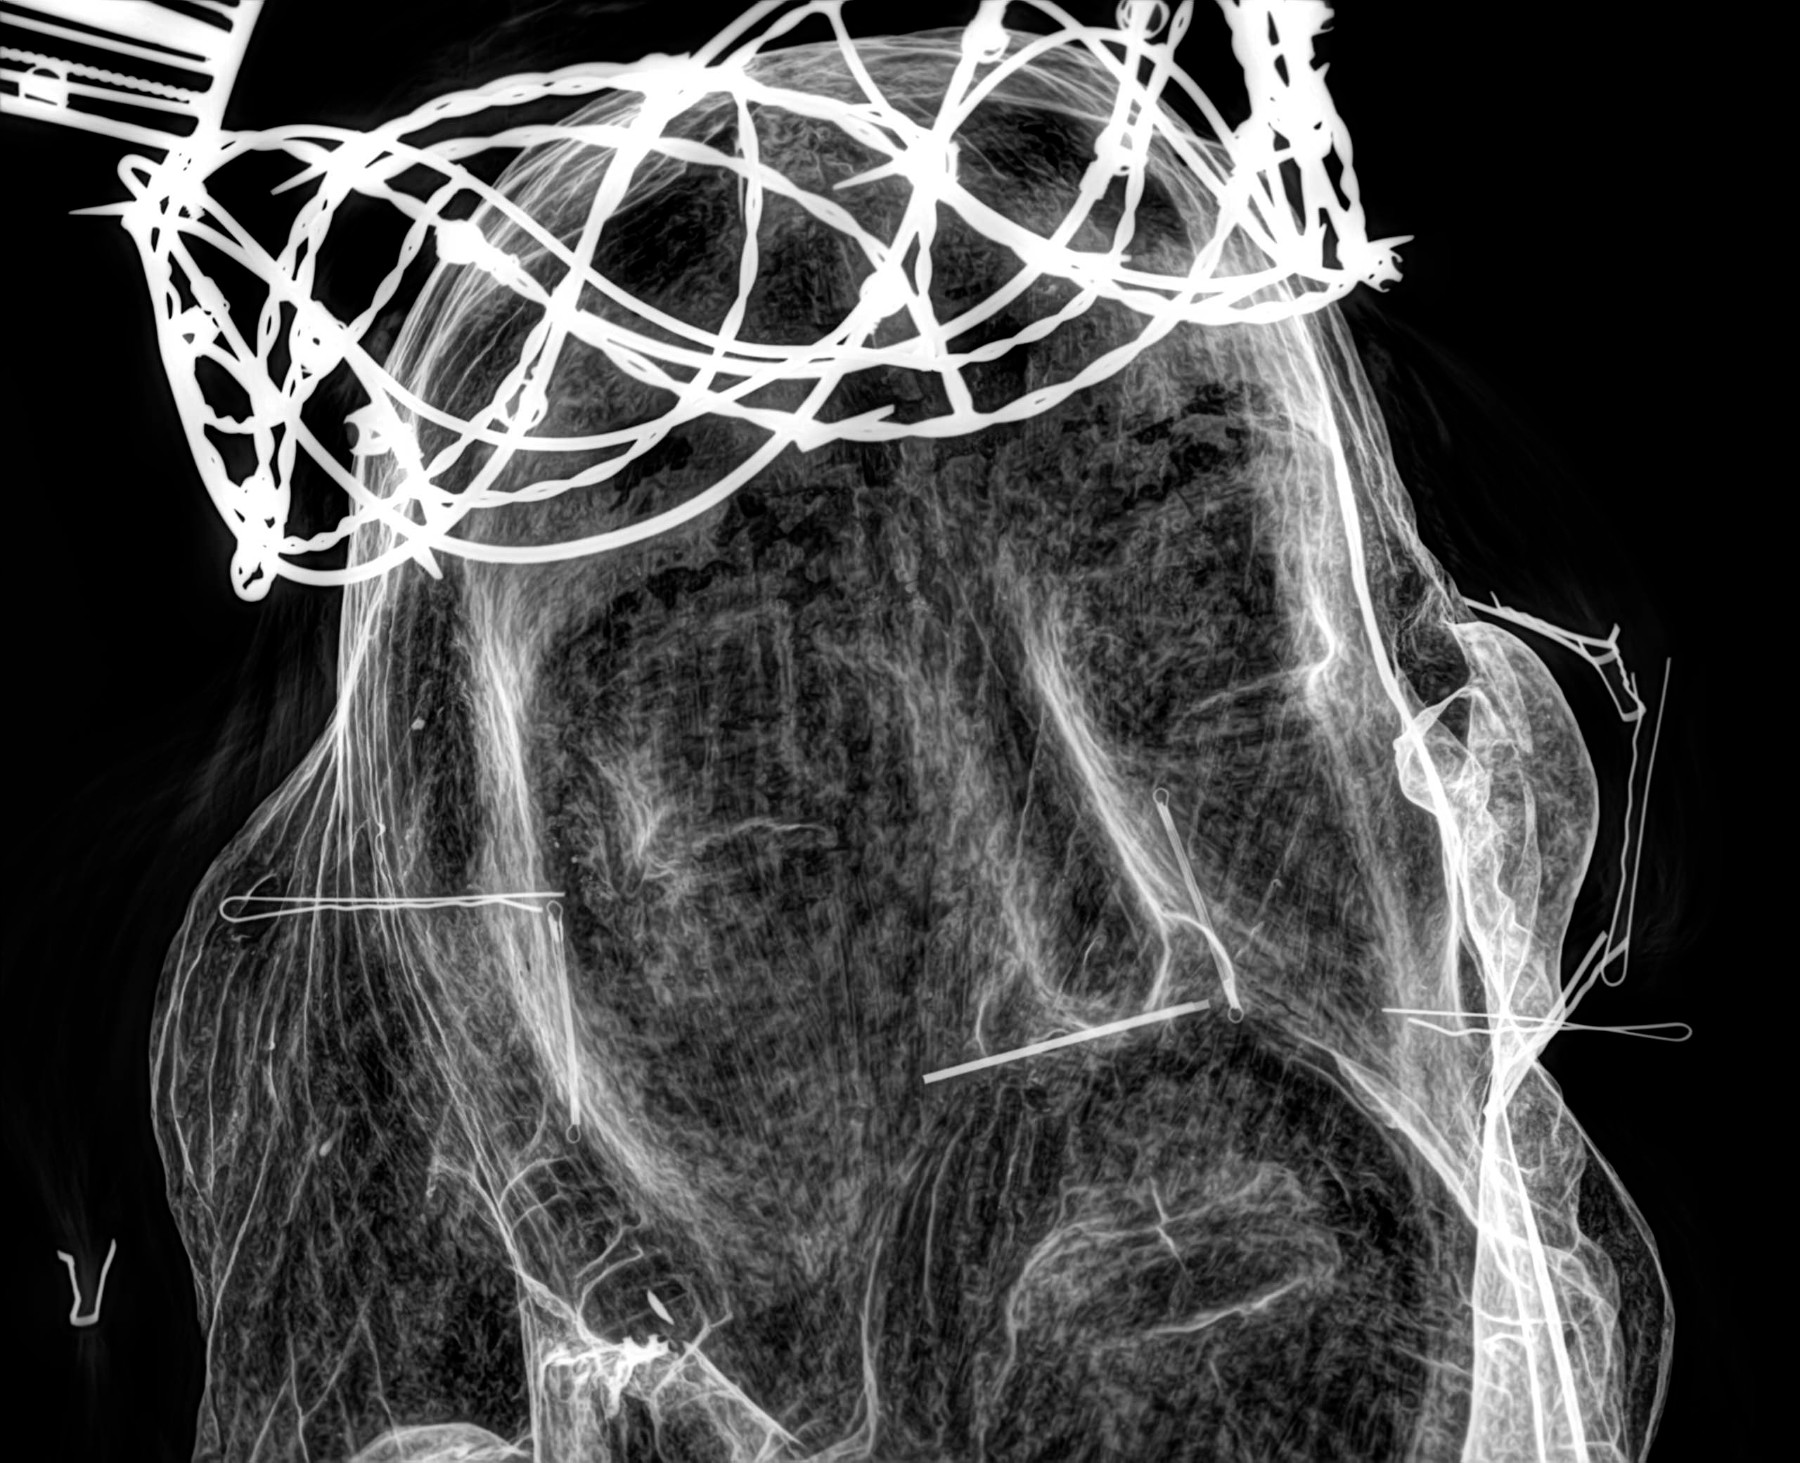

Radiología Digital como Herramienta Complementaria en el Dictamen de Bienes Muebles

Desde el descubrimiento de los rayos “X” y las placas radiográficas por Wilhelm Conrad Roentgen y su posterior difusión a través de la Asociación Físico médica de Wurzburg el 28 de diciembre de 1895, que fue la primera asociación que habló de los nuevos rayos que podían penetrar el cuerpo y fotografiar los huesos, ha habido muchos cambios tanto en la forma de obtener, procesar e incluso en la forma de visualizar, manejar y almacenar las placas radiográficas.